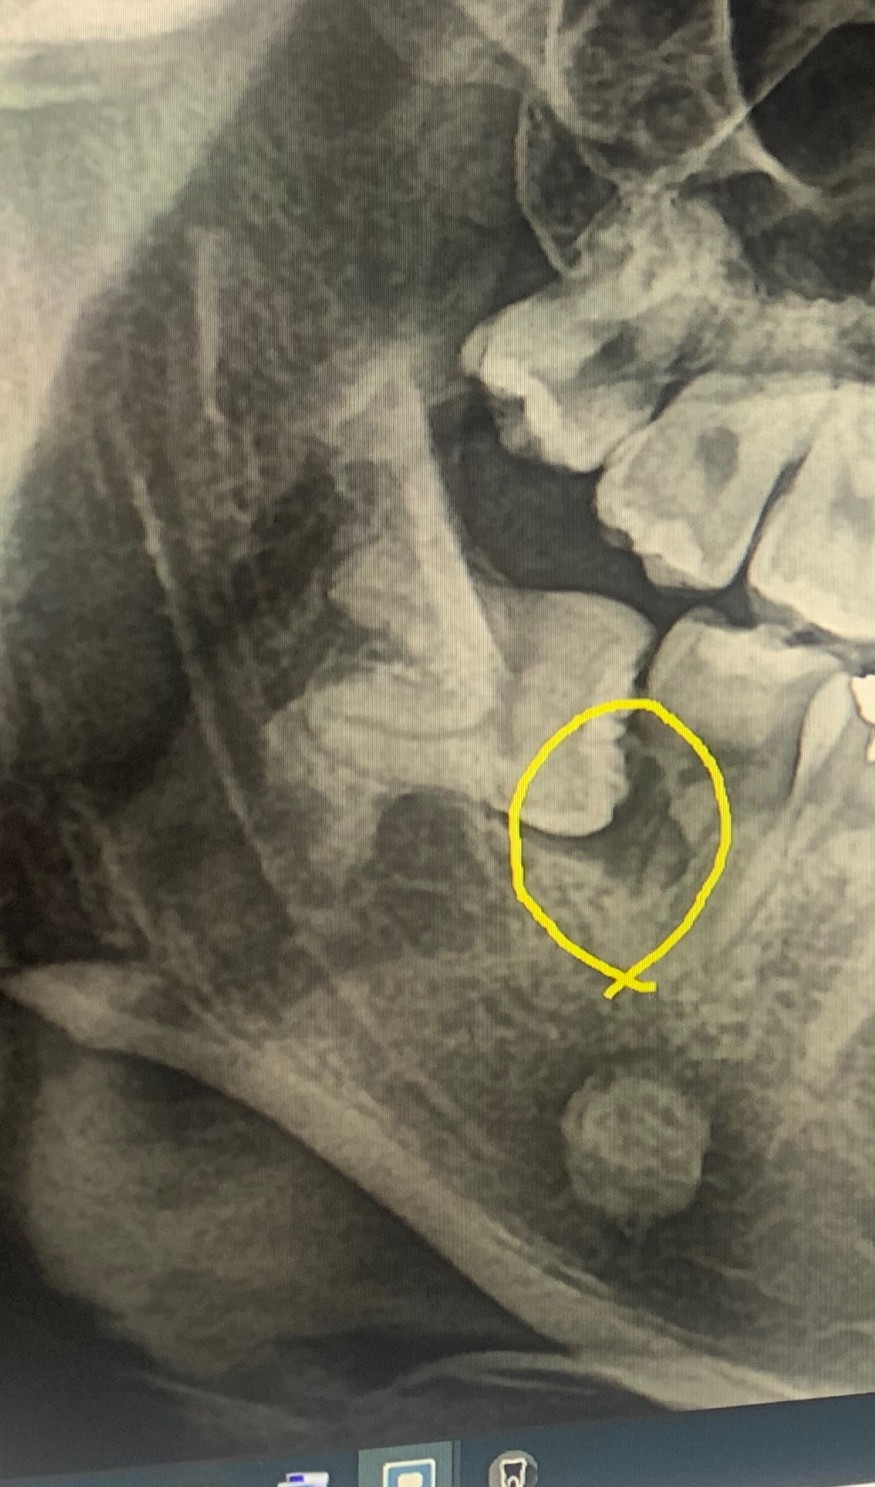

사랑니가 누워서 앞쪽어금니 뿌리를 반이상녹였답니다.